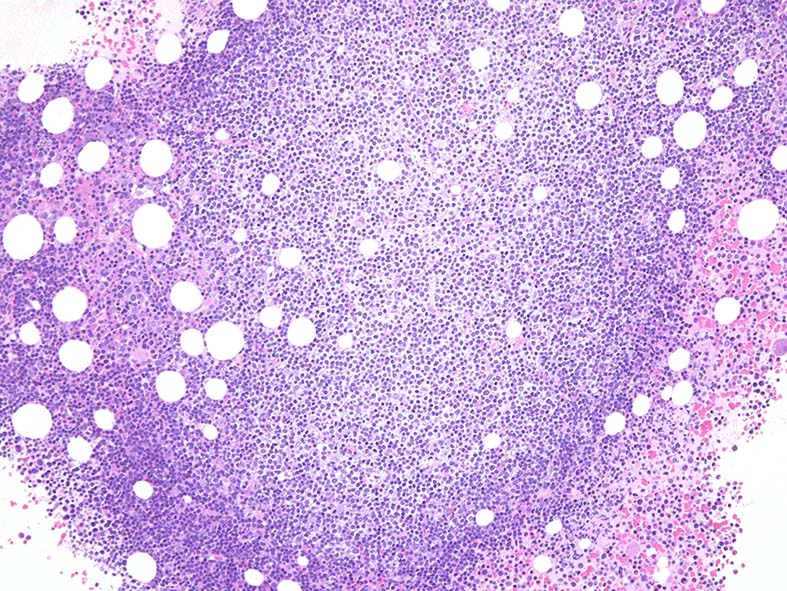

骨髄組織

骨髄には結節性のリンパ球増殖病変が複数形成されている. hpfではmonocytoid B-cellのように淡明な広めの細胞質をもつ.

Mantle cell lymphomaは50-80%の症例がBM involvementを示す. focal, non-paratrabecular pattern (focalな病変はrandomに存在する)が一般的である.

結節中心部増殖細胞はCD20+, cyclinD1+. 核型で t(11;14)(q13;q32)転座が確認された.